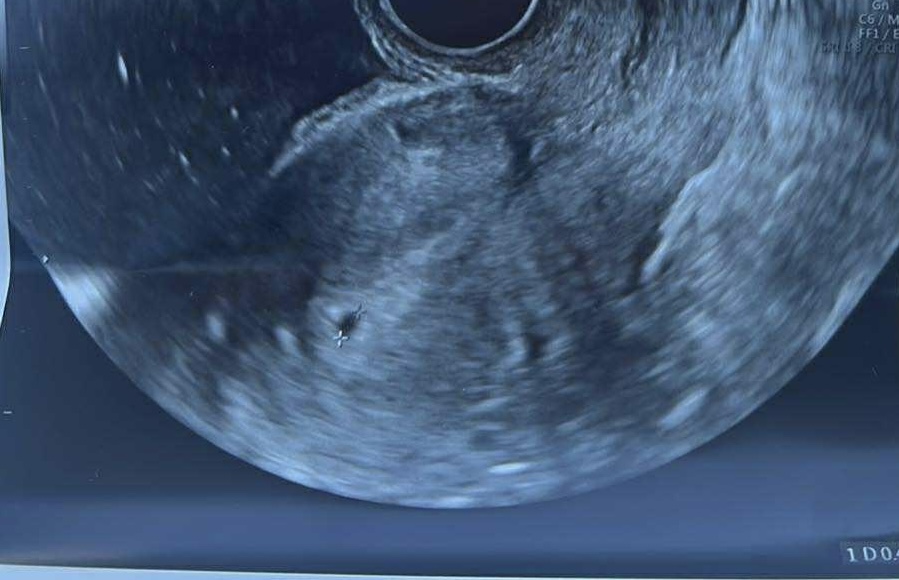

7.1. Videl doktor toto

@olivia20 videl už aj zltkovy vak a zárodok plodu zatiaľ bez akcie srdca